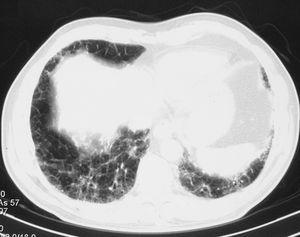

Varón de 71 años, que ingresó en el Servicio de Neumología procedente de una clínica privada. No tenía antecedentes epidemiológicos ni laborales de interés, hábitos tóxicos ni medicación habitual hasta el inicio del cuadro que motivó el ingreso, y tampoco presentaba cardiopatía ni broncopatía previas. Cuatro meses antes de ingresar se encontraba asintomático y se le evaluó en preoperatorio de colecistectomía por radiografía de tórax. Un mes después se le realizó una tomografía axial computarizada de alta resolución (TACAR) ante la sospecha de enfermedad intersticial, y se objetivó afectación intersticial bilateral de predominio basal y periférico, con engrosamiento septal, líneas subpleurales, áreas de panalización y bronquiectasias por tracción, así como adenopatías subcéntricas en el espacio prevascular y paratraqueales derechas (fig. 1). Ante la sospecha de FPI el paciente comenzó tratamiento esteroideo y presentó como complicación descompensación diabética, que precisó tratamiento con antidiabéticos orales. Permaneció asintomático hasta 6 días antes del ingreso actual, cuando comenzó a presentar picos de fiebre de 38 ºC y tos de predominio nocturno hasta hacerse de reposo en las últimas 48 h.

Figura 1. Patrón radiológico, típico de la fibrosis pulmonar idiopática, con afectación intersticial de predominio basal y periférico, engrosamiento septal, líneas subpleurales, áreas de panalización y bronquiectasis por tracción.